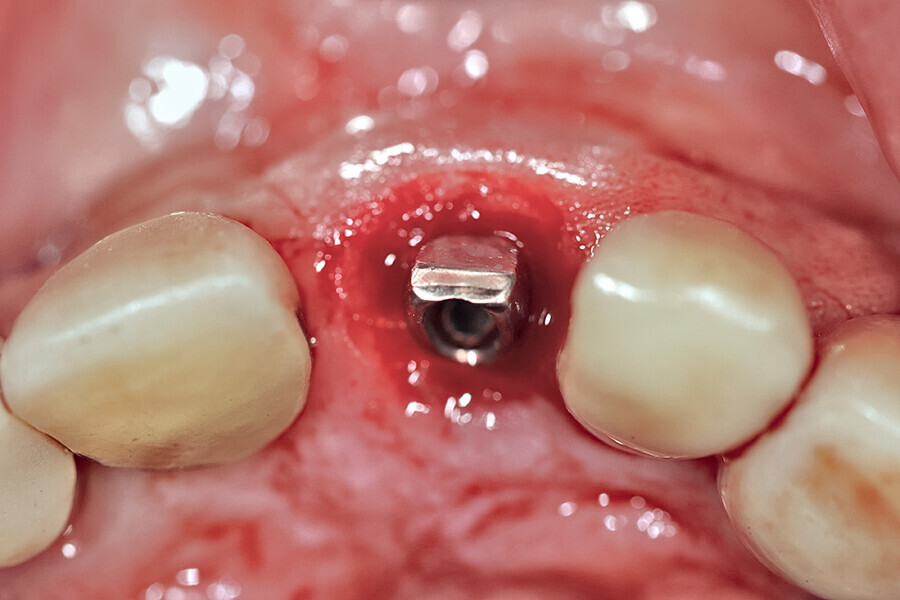

Fig. 24a: Depth control and rotational positioning were accurately

confirmed with the notch indicator on the template corresponding with the insertion tool (a). The occlusal view illustrated that the anti-rotational internal

conical–hexagonal connection was positioned towards the facial aspect (b).

Fig. 24b: Depth control and rotational positioning were accurately